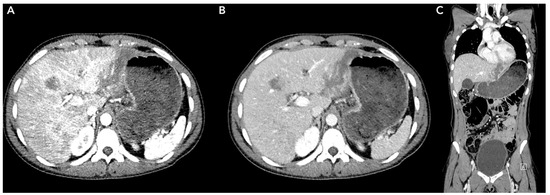

- Dreizin, D.; Chen, T.; Liang, Y.; Zhou, Y.; Paes, F.; Wang, Y.; Yuille, A.L.; Roth, P.; Champ, K.; Li, G.; et al. Added value of deep learning-based liver parenchymal CT volumetry for predicting major arterial injury after blunt hepatic trauma: A decision tree analysis. Abdom. Radiol. 2021, 46, 2556–2566. [Google Scholar] [CrossRef] [PubMed]